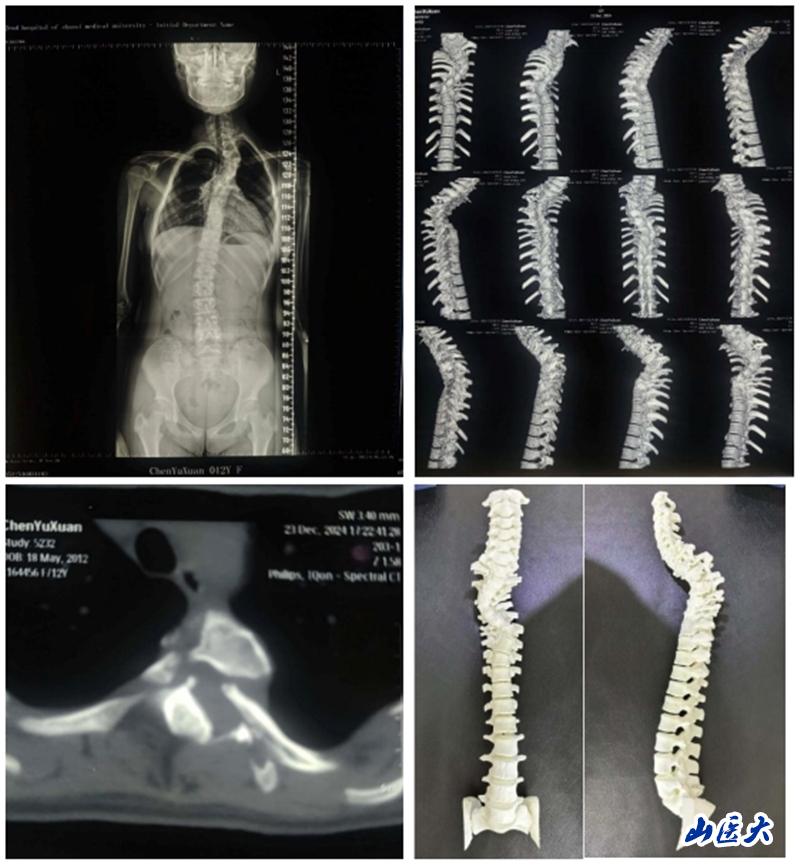

这位小姑娘自幼便全身布满咖啡斑,但因家庭贫困且对疾病认知不足,一直未进行详细检查。2024年7月,其祖母偶然发现孩子脊柱出现明显畸形,遂展开多方求医之路。在得知我校第二医院骨科脊柱畸形专业组薛旭红教授在脊柱侧弯治疗领域造诣颇深后,患者家属慕名而来,前往我校第二医院骨科门诊就诊。薛旭红凭借深厚的医学理论知识和丰富的临床经验,迅速诊断出患者为神经纤维瘤病所致的脊柱侧弯,并立即安排其住院治疗。进一步检查发现,患者因神经纤维瘤病导致椎体骨破坏严重,椎弓根细小,肋骨头变尖并凸入椎管内,手术难度和风险均极高。

面对如此复杂病情,薛旭红教授与赵胜教授带领团队精心策划,为患者量身定制了个性化的手术方案。2024年12月27日,在主治医师董政权、麻醉医师、器械护士王淑珍和巡回护士杜娟的通力协作下,骨科团队成功完成了这场高难度、高风险的手术。